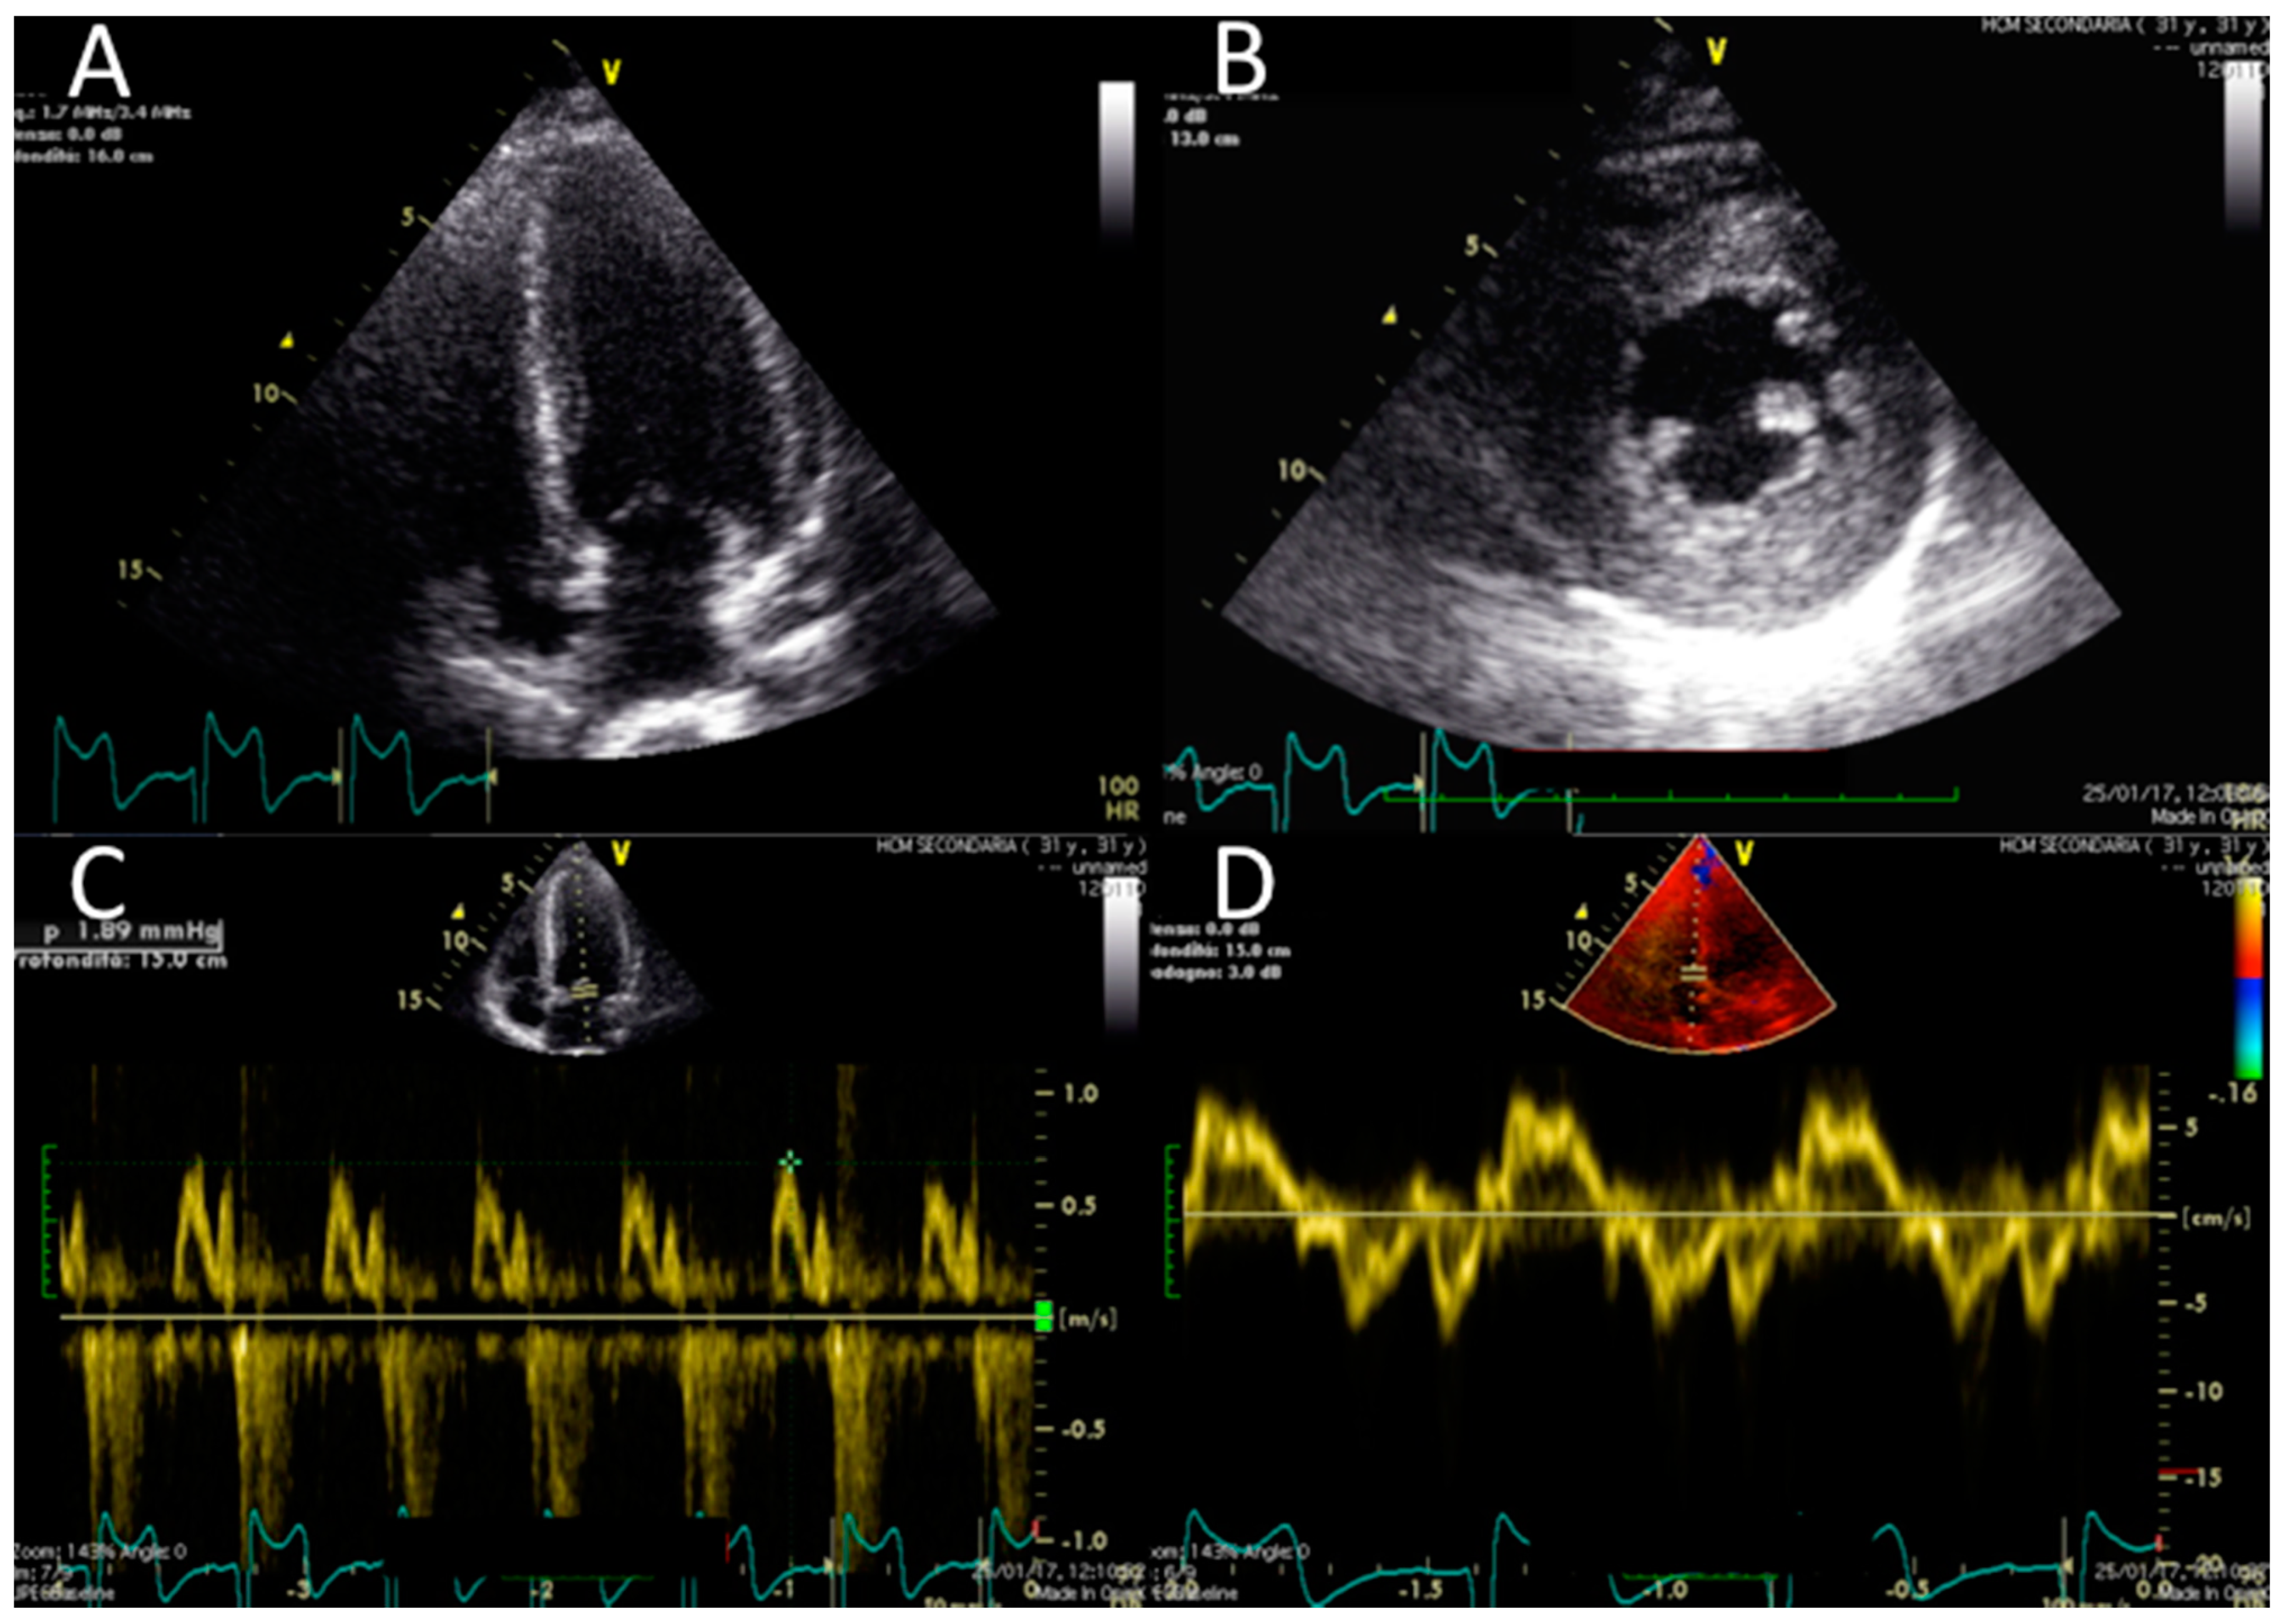

Electrocardiography suggested cardiac hypertrophy, confirmed at cardiac ultrasound, organised in the context of evaluations for kidney transplantation, which disclosed signs of relevant cardiac hypertrophy, out of proportion with her mild hypertension, confirmed at cardiac magnetic resonance (Figure 2, Figure 3 and Figure 4).

Figure 4. Cardiac magnetic resonance. Cardiac magnetic resonance (CMR) confirmed normal LV volume, systolic function and a moderate increase in LV thickness (panel A). No abnormalities in late gadolinium enhancement in the horizontal long-axis view (B) or vertical long-axis view (C) were found.